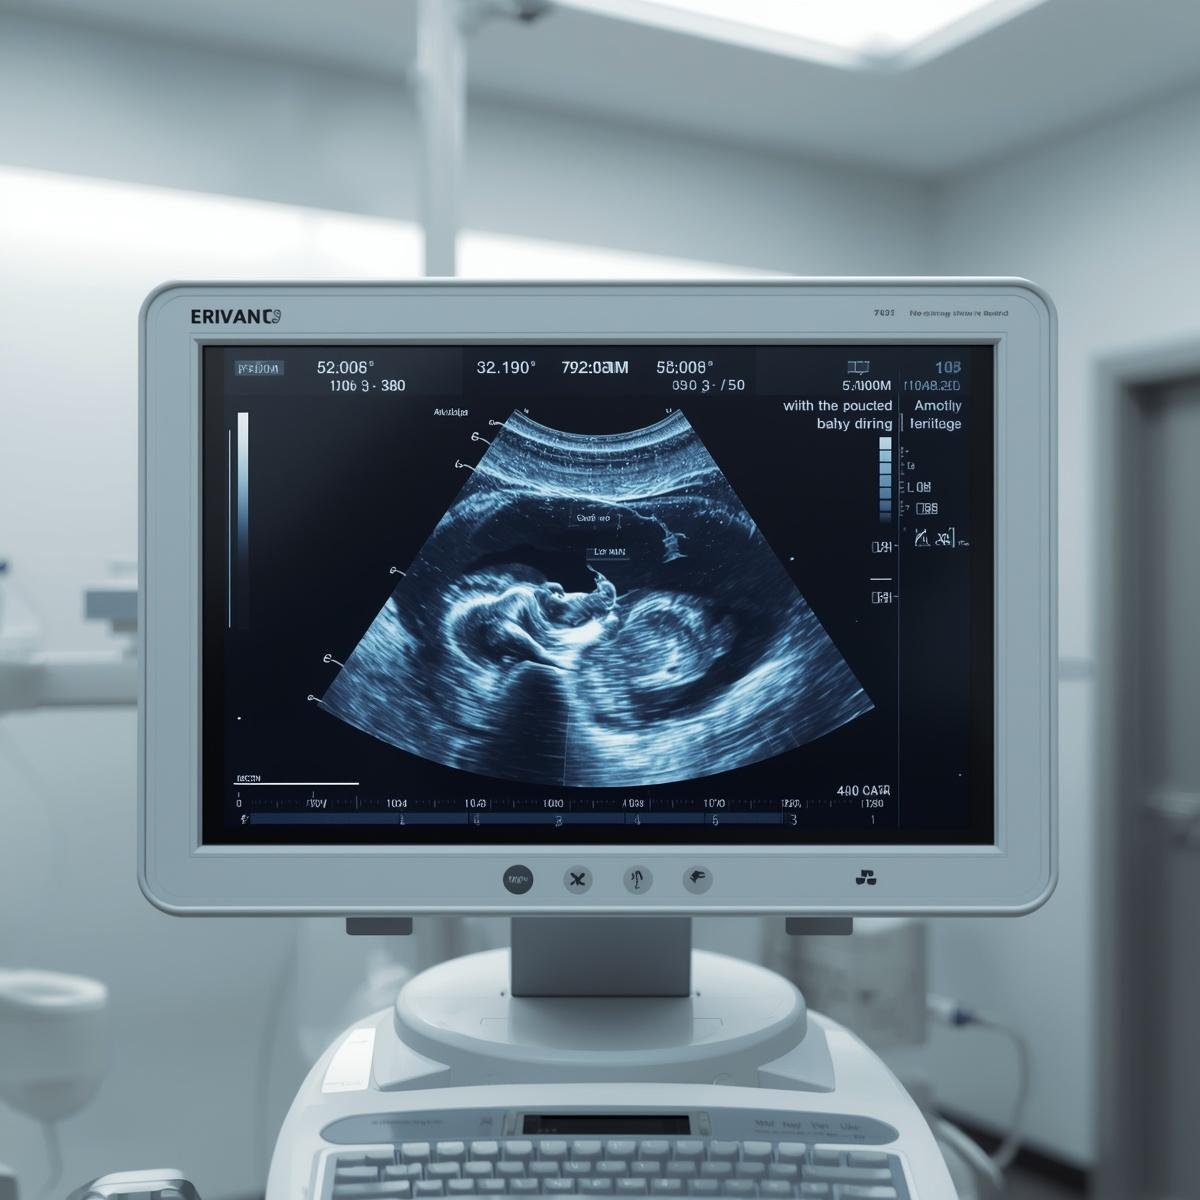

Regular check-ups, ultrasounds, and diagnostic tests help monitor the health of both mother and baby throughout pregnancy.

Fetal Monitoring

Advanced tests help track the baby’s growth, heartbeat, and overall well-being.